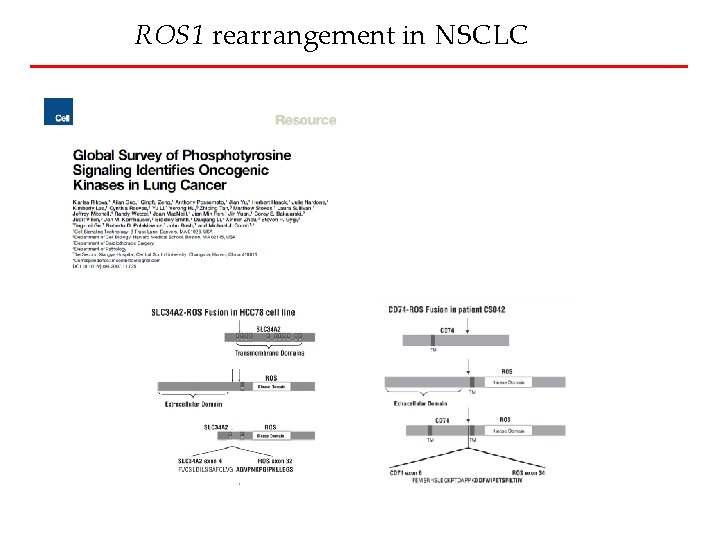

ROS 1 rearrangement in NSCLC

ROS 1 rearrangement in NSCLC